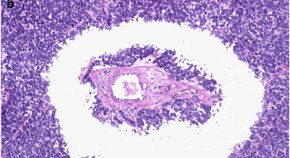

Patients with bladder cancer have a substantially increased risk of prostate cancer, compared with that of the general male population, and a diagnosis of concomitant prostate cancer can contribute to inferior outcomes, particularly in patients with muscle-invasive bladder cancer. Here, the authors describe the outcomes of such patients, in addition to the optimal treatment and management strategies and future research needs.